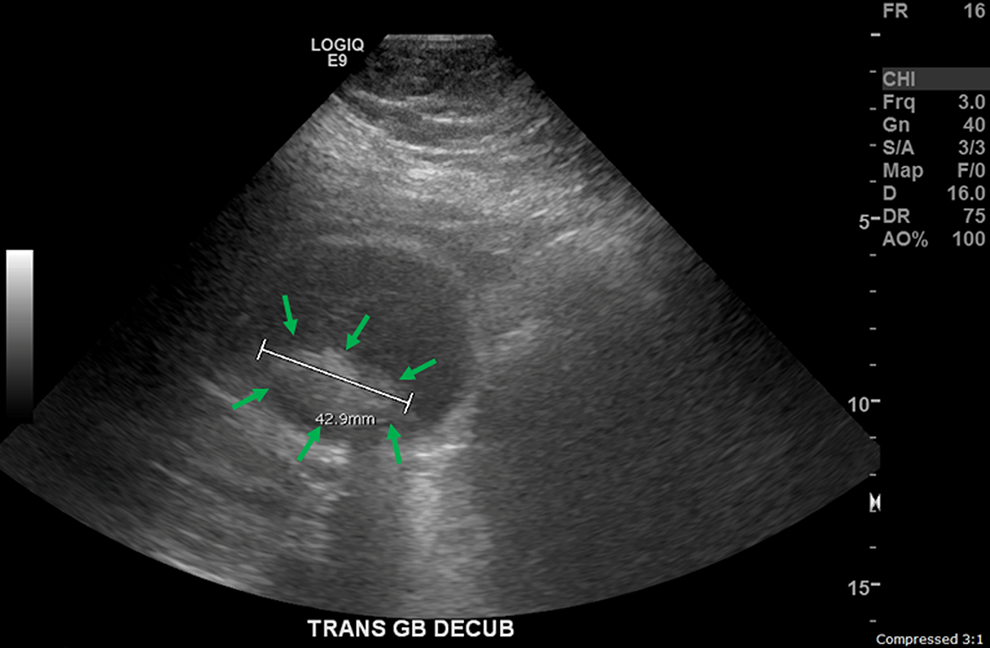

The patient underwent an ultrasound of the GB as shown in Figure 1 (shadowing gallstones seen and the largest one is about 43 mm in greatest diameter). Abdominal ultrasound revealed cholelithiasis and biliary sludge with GB wall thickening and a positive sonographic Murphy sign, concerning for acute cholecystitis with cholelithiasis. Borderline hepatomegaly was seen.

Ultrasound image shows shadowing gallstones. The largest gallstone (green arrows) is about 43 mm in greatest diameter as labeled in the picture. Combined with patient’s clinical features, the diagnosis of acute cholecystitis and cholelithiasis was made.